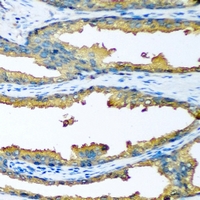

Immunohistochemical analysis of Cytochrome P450 46A1 staining in human prostate cancer formalin fixed paraffin embedded tissue section. The section was pre-treated using heat mediated antigen retrieval with sodium citrate buffer (pH 6.0). The section was then incubated with the antibody at room temperature and detected using an HRP conjugated compact polymer system. DAB was used as the chromogen. The section was then counterstained with haematoxylin and mounted with DPX.